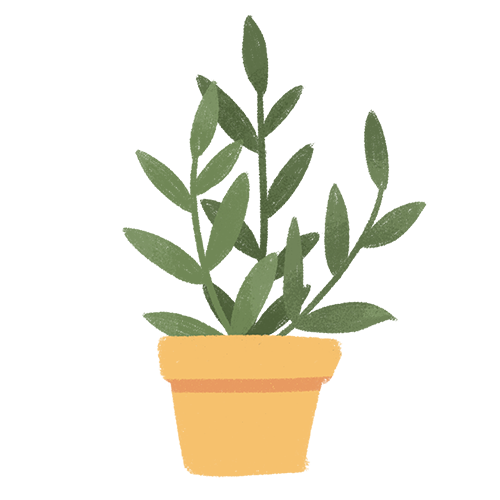

關(guān)于腰椎間盤突出  腰椎間盤突出癥是纖維環(huán)破裂后髓核突出壓迫神經(jīng)根造成以腰腿痛為主要表現(xiàn)的疾病。腰椎間盤退行性改變或外傷所致纖維環(huán)破裂,髓核從破裂處脫出,壓迫腰椎神經(jīng),從而出現(xiàn)腰腿放射性疼痛。  病因: 一、退行性變: 目前認(rèn)為,其基本病因是腰椎間盤的退行性變。退行性變是一切生物生、長、衰、亡的客觀規(guī)律,由于腰椎所承擔(dān)的特殊的生理功能,腰椎間盤的退行性變比 其他組織器官要早,而且進(jìn)展相對要快。這個過程是一個長期,復(fù)雜的過程。所謂腰椎間盤退行性改變:即由于椎間盤受體重的壓迫,加上腰部又經(jīng)常進(jìn)行彎曲、后伸等活動,易造成椎間盤的擠壓和磨損,尤其是下腰部的椎間盤,從而產(chǎn)生退行性改變。腰椎間盤退行性改變是本病發(fā)生的基礎(chǔ)。 二、其他因素: 1、外力作用:在日常生活和工作中,部分人往往存在長期腰部用力不當(dāng)、過度用力姿勢或體位的不正確等情況。例如長期從事彎腰工作的煤礦工人和建筑工人需經(jīng)常彎腰提舉重物。這些長期反復(fù)的外力造成的損傷日積月累地作用于椎間盤,加重了退變的程度。 2、椎間盤自身解剖因素的弱點: (1) 椎間盤在成人之后逐漸缺乏血液循環(huán),修復(fù)能力也較差,特別是在退變產(chǎn)生后,修復(fù)能力更加微弱。 (2) 椎間盤后外側(cè)的纖維環(huán)較為薄弱,而后縱韌帶在腰5、骶1平面時寬度顯著減少,對纖維環(huán)的加強(qiáng)作用明顯減弱。 (3) 腰骶段先天異常:腰骶段畸形可使發(fā)病率增高,這些異常造成椎間隙寬度不等,并常造成關(guān)節(jié)突出,關(guān)節(jié)受到更多的旋轉(zhuǎn)勞損,使纖維環(huán)受到的壓力不一,加速退變。 3、種族、遺傳因素:有色人種發(fā)病率較低,例如印第安人和非洲黑人等發(fā)病率較其他民族明顯要低。  2 病理 腰椎間盤突出癥的病理變化過程大致可分為三個階段: 1、突出前期:髓核因退變和損傷可變成碎塊狀物,或呈瘢痕樣結(jié)締組織,變性的纖維環(huán)可因反復(fù)損傷而變薄變軟或產(chǎn)生裂隙。此期病人可有腰部不適或疼痛,但無放射性下肢痛。也有的人原無病變,可因一次大的暴力引起髓核突出。 2、突出期:外傷或正常的活動使椎間盤壓力增加時,髓核從纖維環(huán)薄弱處或破裂處突出。突出物刺激或壓迫神經(jīng)根即發(fā)生放射性下肢痛,或壓迫馬尾神經(jīng)發(fā)生大小便功能障礙。在老 年患者,可因椎間盤退變,整個纖維環(huán)變得軟弱松弛,椎間盤可呈彌漫性向周圍膨出。 3、突出晚期:腰椎間盤突出后,病程較長者,椎間盤本身和其他鄰近結(jié)構(gòu)均可發(fā)生各種繼發(fā)性病理改變。 3 誘發(fā)因素 腰椎間盤突出癥的基本因素是椎間盤退變,但某些誘發(fā)因素可致使椎間隙壓力增高,引起髓核突出。此種誘發(fā)因素常與以下因素有關(guān): 1. 年齡因素:腰椎間盤突出癥的好發(fā)年齡在30-50歲,平均手術(shù)年齡在40歲,因此退變可能是其重要因素。 2. 身高與性別:有人認(rèn)為身材過高也會易發(fā)腰突癥,而男性發(fā)病率是女性的5倍。 3. 增加腹壓:臨床上有約1/3的病人在發(fā)病前有明確的增加腹壓的因素,如劇烈的咳嗽、噴嚏、屏氣、用力排便等。使腹壓增高,破壞了椎節(jié)與椎管之間的平衡狀態(tài)。 4. 不良體位:人在完成各種工作時,需要不斷更換各種體位以緩解腰部壓力,如長期處于某一體位不變,即可導(dǎo)致局部的累積性損傷。特別是長期處于不良姿勢更容易誘發(fā)本病。 5. 職業(yè)因素:重體力勞動者發(fā)病率最高,白領(lǐng)勞動者最低。汽車駕駛員由于長期處于顛簸和振動狀態(tài),椎間盤承受的壓力大且反復(fù)變化,也易誘發(fā)椎間盤突出。 6. 受寒受濕:寒冷或潮濕可引起小血管收縮、肌肉痙攣,使椎間盤的壓力增加,可能造成退變的椎間盤破裂。     癥狀: 腰椎間盤突出癥患者最多見的癥狀為疼痛,可表現(xiàn)為腰背痛、坐骨神經(jīng)痛,典型的坐骨神經(jīng)痛表現(xiàn)為由臀部、大腿后側(cè)、小腿外側(cè)至跟部或足背的放射痛。據(jù)臨床統(tǒng)計,約95%的腰突癥患者有不同程度的腰痛,80%的患者有下肢痛。特別是腰痛,不僅是腰椎間盤突出最常見的癥狀,也是最早出現(xiàn)的癥狀之一。    檢查: 1、X線:腰椎間盤所包括的髓核、纖維環(huán)和軟骨板密度均較低,在X線下并不顯影,因此臨床上腰突癥患者的腰椎X線平片可僅有一些非特異性的變化,甚至無異常變化。因此單純腰椎平片并不能作為有無腰椎間盤突出癥的直接依據(jù),但X線能發(fā)現(xiàn)腰椎的退行性改變和結(jié)構(gòu)異常,對提示椎間盤的退變有重要意義,并且能排除其他的一些腰椎疾患,如腰椎結(jié)核、腫瘤和腰椎滑脫等。典型的腰椎間盤突出癥患者通過病史、體征和X線平片即能作出初步的診斷。 2、CT檢查:腰椎的CT可以清楚地顯示椎間盤突出的部位、大小、形態(tài)和神經(jīng)根、硬脊膜受壓的情況,同時還可顯示黃韌帶肥厚、小關(guān)節(jié)增生、椎管和側(cè)隱窩狹窄等情況。對腰椎間盤突出癥診斷的準(zhǔn)確率達(dá)到80%-92%。 3、核磁共振(MRI):核磁共振沒有輻射,可以多方位成像(橫斷面、冠狀面、矢狀面和斜面),對解剖細(xì)節(jié)顯示較好,對組織結(jié)構(gòu)的細(xì)微病理變化更敏感(如骨髓的浸潤),可以排除神經(jīng)和脊柱腫瘤等。對于一些落到椎管的髓核組織也不會遺漏。 4、脊髓造影:脊髓造影利用椎管內(nèi)蛛網(wǎng)膜下腔的空隙,注入造影劑后在X線下攝片,顯示椎管內(nèi)部結(jié)構(gòu)。目前常用水溶性造影劑,能較清晰地顯示硬膜腔、馬尾神經(jīng)和神經(jīng)根鞘,對腰椎間盤突出癥的診斷可達(dá)90%左右,主要X線表現(xiàn)為硬膜囊壓迫征象和神經(jīng)根鞘壓迫征象。但由于CT和MRI在臨床的廣泛應(yīng)用,無創(chuàng)傷且診斷率更高,脊髓造影在臨床上的應(yīng)用已經(jīng)大大減少,而且由于它副作用較大,甚至可能造成截癱等嚴(yán)重情況,目前主張慎重選用。 5、肌電圖:肌電圖是對周圍神經(jīng)與肌肉的電生理檢查方法,可用于觀察并記錄肌肉在靜止、主動收縮和支配其的周圍神經(jīng)受刺激時的電活動,同時也可用來測量周圍神經(jīng)的傳導(dǎo)速度。在腰椎間盤突出癥上,肌電圖主要通過檢查雙下肢肌肉的興奮性來反映相應(yīng)神經(jīng)根的狀態(tài),并根據(jù)異常電活動的分布范圍來判斷椎間盤突出和神經(jīng)根受壓的節(jié)段。在脊神經(jīng)根和馬尾神經(jīng)受壓的病人,肌電圖陽性率可達(dá)80%-90%,但與CT和MRI相比并不是首選的檢查手段,可用于輔助診斷和判斷神經(jīng)根的受壓情況,同時也可以用來作為判斷治療后神經(jīng)根恢復(fù)情況的指標(biāo)之一。    預(yù)防: 腰椎間盤突出癥是在退行性變基礎(chǔ)上積累傷所致,積累傷又會加重椎間盤的退變,因此預(yù)防的重點在于減少積累傷。 日常注意事項: 1.平時要有良好的坐姿,睡眠時的床不宜太軟。 2.長期伏案工作者需要注意桌、椅高度,定期改變姿勢。 3.職業(yè)工作中需要常彎腰動作者,應(yīng)定時伸腰、挺胸活動,并使用寬的腰帶。 4.應(yīng)加強(qiáng)腰背肌訓(xùn)練,增加脊柱的內(nèi)在穩(wěn)定性,長期使用腰圍者,尤其需要注意腰背肌鍛煉,以防止失用性肌肉萎縮帶來不良后果。 5.如需彎腰取物,最好采用屈髖、屈膝下蹲方式,減少對腰椎間盤后方的壓力。    治療: (一)中醫(yī)外敷療法: 腰椎間盤突出可以外貼 腰突正骨膏,其有效成分可透入皮膚產(chǎn)生活血,止痛,化淤,通經(jīng)走絡(luò),開竅透骨,祛風(fēng)散寒等效果,并通過藥物的歸經(jīng)作用而調(diào)理機(jī)體陰陽平衡,滲透于表皮,刺激神經(jīng)末梢,促進(jìn)局部血液微循環(huán),扶正固本、改善體質(zhì),從根本上、全方位針對腰椎疾病病機(jī)特點而發(fā)揮療效,改善病變周圍組織營養(yǎng),起到修復(fù)骨病組織的作用,最終達(dá)到治療目的。 (二)自我治療: 1.腹肌鍛煉: 也就是仰臥起坐。每次做十個,每天三次。(可根據(jù)患者的體質(zhì)來定,不可逞強(qiáng))。 2.交叉扭腰: 兩腳分開與肩寬,腳尖向內(nèi)兩臂伸直,一手在體側(cè),一 手舉過頭頂。如果右手在上,先向左側(cè)后方擺。左側(cè)相反。于此同時腰部也隨之扭動,左右各100次。 3.抱膝觸胸: 處于仰臥位,雙膝屈曲,手抱住膝部,使盡量靠近胸部,然后放下,一上一下為一個動作,可持續(xù)30個。 4.腰背肌鍛煉: 處于平臥,雙膝彎曲放在床上,然后用力將臀部抬起,離開床面10厘米。這時您會感覺到腰背部在用力,堅持5秒鐘,反復(fù)10下。  (三)非手術(shù)治療: 非手術(shù)療法是治療腰椎間盤突出癥的基本療法,約80%以上的患者經(jīng)保守治療均可得到緩解和痊愈。其主要療法有: 1.日常家庭治療:早期腰椎間盤突出癥,癥狀輕微,不需要做特殊的治療。第一,注意臥床休息,避免腰椎受外力壓迫,第二,應(yīng)用其他方法積極鍛煉腰部肌肉力量。 2.牽引治療; 3.推拿按摩治療; 4.物理治療; 5.消炎鎮(zhèn)痛藥物; 6.減輕神經(jīng)根水腫藥物。 (四)推拿治療: 1.解除腰臀部肌肉痙攣 2.拉寬椎間隙,降低盤間壓力 3.增加椎間盤外壓力 4.調(diào)整后關(guān)節(jié),松解粘連 5.促使受損傷的神經(jīng)根恢復(fù)功能 (五)微創(chuàng)治療: 微創(chuàng)治療方法的目的是消除腰椎間盤突出的髓核以解除對神經(jīng)的壓迫。微創(chuàng)治療技術(shù)采用可視設(shè)備,創(chuàng)口不足一厘米有些甚至不足一毫米。消融或摘除髓核,從根本上解除致病因素,因而能夠取得很好的效果。 (六)手術(shù)治療: 腰椎間盤突出癥的手術(shù)原則是嚴(yán)格無菌操作,盡量保留不必去除的骨結(jié)構(gòu)和軟組織結(jié)構(gòu),以最小的創(chuàng)傷達(dá)到足夠的顯露,仔細(xì)徹底地去除病變組織,達(dá)到治療目的。   綠柏相關(guān)產(chǎn)品:  懸吊訓(xùn)練療法是康復(fù)醫(yī)學(xué)中以持久改善肌肉骨骼疾病為目的的,應(yīng)用主動治療和訓(xùn)練的一個總的概念整合,是一種運(yùn)動感覺的綜合訓(xùn)練系統(tǒng),包括診斷與治療兩大系統(tǒng)。 產(chǎn)品特點: 1.電腦軟件管理系統(tǒng),涵蓋患者信息管理、評估、訓(xùn)練、量表、報告、視頻教學(xué)六大模塊,輕松實現(xiàn)評估與訓(xùn)練一體化管理; 2.多點多軸設(shè)計,滿足不同治療方案設(shè)計; 3.懸吊工作站及各個懸吊點,均能實現(xiàn)任意位置移動,一鍵解鎖,省時省力; 4.實時力反饋,精準(zhǔn)量化弱鏈測試及懸吊治療全過程,給治療師及患者最直觀的效果呈現(xiàn); 5.智能神經(jīng)肌肉促通裝置,可根據(jù)評估結(jié)果設(shè)置治療模式、頻率、時間等相關(guān)參數(shù),讓懸吊康復(fù)更加高效有針對性; 6.外觀高端大氣,結(jié)構(gòu)穩(wěn)固,給患者安全保障,增加治療信心。  |